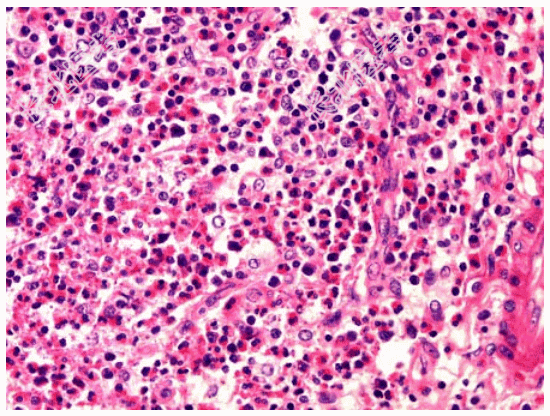

- [材料题] 患者男性,53岁,腹胀,返酸,嗳气半年。胃镜检查见胃窦部黏膜稍粗糙,并可见小片状糜烂。

- 简答题1、镜检如图所示黏膜内大量炎细胞浸润,以哪一类炎细胞为主?